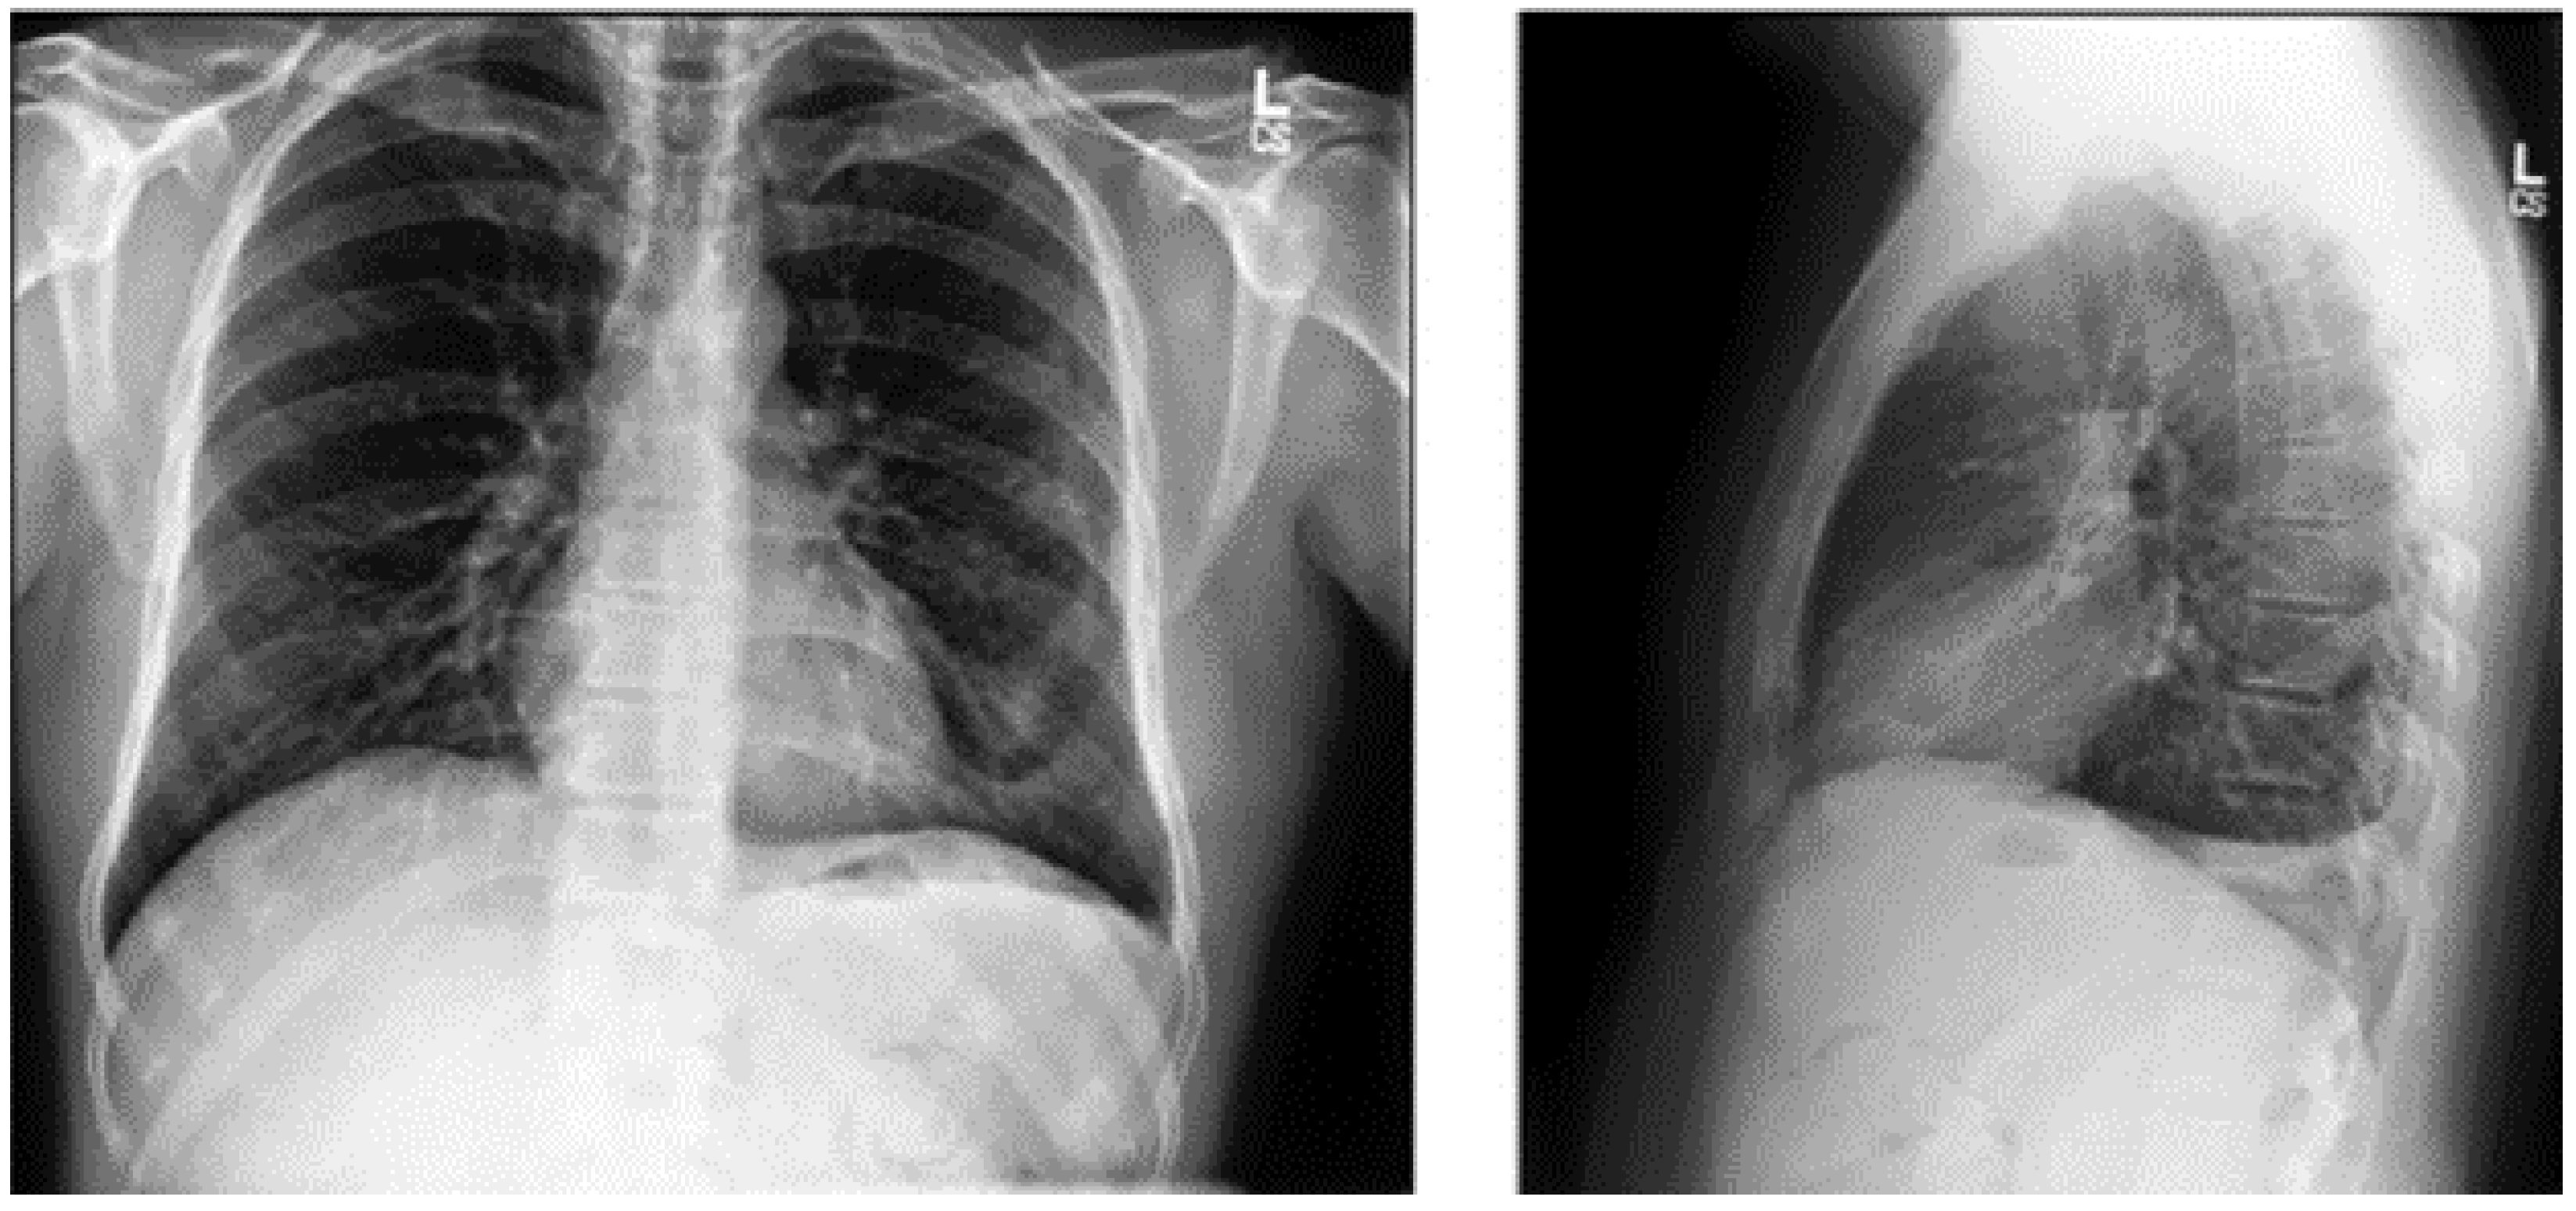

3.1.4. PadChest Dataset

This is a comprehensive and valuable resource for medical imaging research, consisting of over 160,000 CXR images obtained from 67,000 patients [28,29]. The samples from the PadChest dataset are shown in Figure 6. These images were collected between 2009 and 2017 at San Juan Hospital in Spain, representing various cases and clinical scenarios [30]. The dataset includes images captured in six position views, providing versatility for various radiological studies. Additionally, it contains extensive metadata detailing information about image acquisition techniques and patient demographic characteristics, further enhancing its utility for diverse research applications.

Figure 6.

PadChest dataset samples [28].